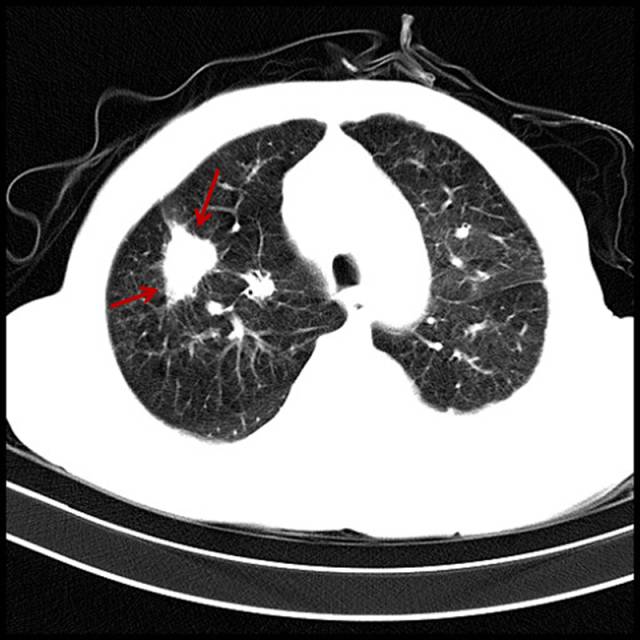

吸烟导致肺癌

男,79岁,吸烟。

图片

图15

弥漫性肺气肿,右上肺周围型肺癌。再常见不过了。